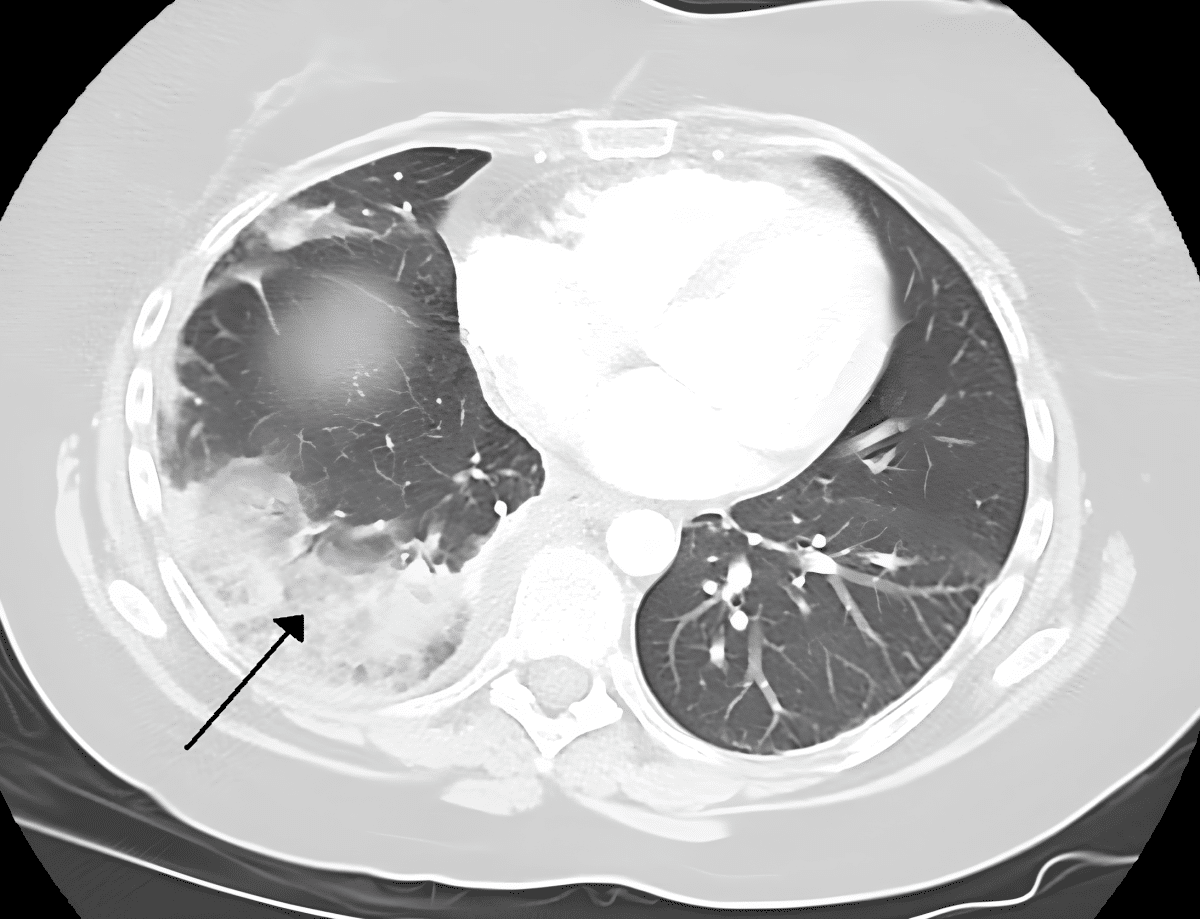

Гибель тканей легкого из-за тромбоэмболии легочной артерии / © James Heilman, MD, en.wikipedia.org